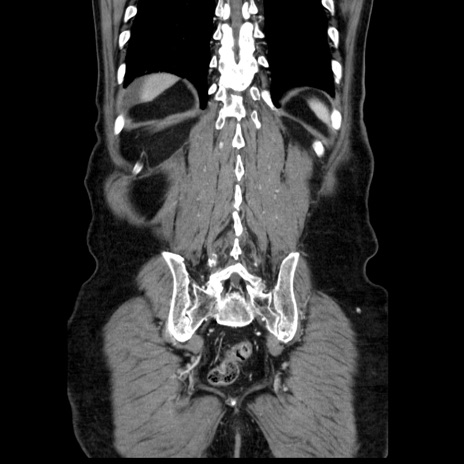

症例30(冠状断像)

【症例】80歳代男性

【主訴】臍周囲痛

【現病歴】約6時間前から臍下部痛が出現。次第に腹部膨隆・背部痛も生じてきたため来院。背部痛の場所は変化しない。

【身体所見】意識清明、BT 36.3℃、BP  131/87mmHg、P 87bpm、SpO2 100%(RA)、臍周囲自発痛・圧痛あり、反跳痛なし、自発痛部位に一致して板状硬あり、腹部膨隆、腸雑音減弱、CVA tenderness両側陰性。

【データ】WBC 19600、CRP 0.33